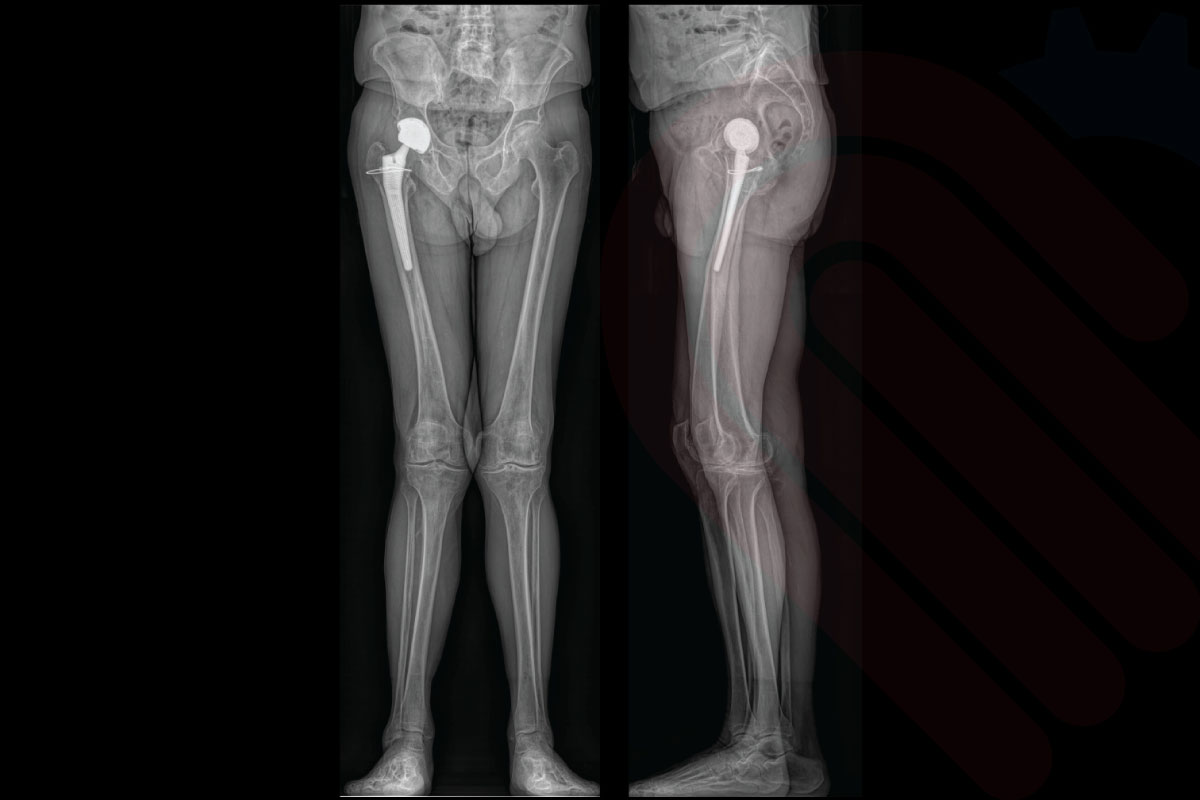

EOSedge®, ortopedi ve kas-iskelet sistemi tanısında yeni bir standart belirleyen, düşük doz radyasyonla yüksek çözünürlüklü biplanar görüntüleme sağlayan gelişmiş bir sistemdir. Skolyoz, kalça-diz deformiteleri, alt ekstremite hizalanma bozuklukları ve travma sonrası değerlendirmelerde; 1:1 oranlı, distorsiyonsuz ve yük taşıyan pozisyonda alınan görüntülerle cerrahlara güvenilir tanı ve cerrahi planlama imkânı sunar.

EOSedge, hastanın başından ayak bileğine kadar tek pozisyonda tam vücut görüntüleme imkânı sunar. Geniş görüş alanı ve dikey tarama teknolojisi sayesinde tüm iskelet yapısı doğal yük taşıma pozisyonunda görüntülenir. Bu, skolyoz, bacak uzunluğu farklılıkları ve eklem hizalanma bozukluklarının değerlendirilmesinde kritik öneme sahiptir.

EOSedge, aynı anda hem önden (AP) hem de yandan (lateral) yüksek çözünürlüklü görüntüler alabilen biplanar görüntüleme teknolojisine sahiptir. Bu sayede, hasta tek bir pozisyonda dururken iki farklı perspektiften tam iskelet görüntüsü elde edilir. Biplanar yapı, anatomik detayların doğru şekilde değerlendirilmesini sağlar ve cerrahi planlamalarda yüksek doğruluk sunar.

Ayrıca, 1:1 oranlı doğrudan görüntüleme özelliği ile çekilen görüntülerde ölçeklendirme hatası ortadan kalkar. Bu, skolyoz ölçümleri, alt ekstremite uzunluk analizleri ve protez planlamalarında kritik öneme sahiptir. Cerrahlar, hastanın gerçek boyutlarına sadık kalınarak elde edilmiş görüntüler üzerinden çalıştığı için, operasyon sonrası beklenmedik uyumsuzluk riskleri en aza iner.

EOSedge, tek bir pozisyonda hastanın tüm vücut iskelet sistemini kapsayan geniş bir görüntüleme alanı sunar. Bu sayede skolyoz, alt ekstremite uzunluk farkı, postür bozuklukları gibi durumlar tek taramada eksiksiz olarak değerlendirilebilir. 1.80 metreye kadar dikey ve 50 cm yatay alanı kapsayabilen sistem, hem pediatrik hem yetişkin hastalarda tekrarlayan çekim ihtiyacını azaltır. Bu geniş kapsama, tüm vücut hizalamasının bütüncül olarak incelenmesine ve multidisipliner tedavi planlamasına olanak tanır*.

hipEOS, EOSedge sistemi ile elde edilen düşük doz, gerçek boyutlu biplanar görüntüler üzerinden kalça ekleminin 3D analizini ve cerrahi planlamasını yapan gelişmiş bir yazılımdır. Total kalça protezi (THA) ve diğer kalça rekonstrüksiyon cerrahilerinde, asetabular kupa açısı, femoral stem pozisyonu, bacak uzunluğu farkı ve offset gibi kritik parametreleri preoperatif olarak belirlemenize olanak tanır. Yük taşıyan pozisyonda elde edilen görüntüler sayesinde, implant yerleşimi ve pozisyonlaması hastanın doğal biyomekaniğine en uygun şekilde planlanabilir. Klinik veriler, hipEOS planlaması ile gerçekleştirilen operasyonlarda postoperatif bacak uzunluğu eşitliği ve komponent pozisyon doğruluğunda anlamlı iyileşmeler olduğunu göstermektedir*.